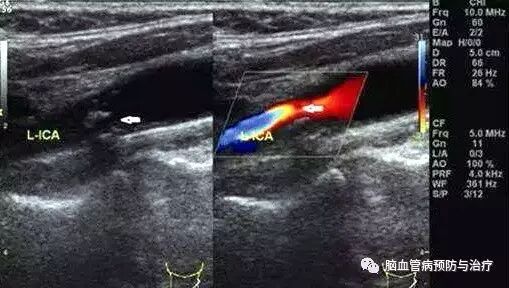

脑血管超声只是一个初步的脑血管病变的筛查,其结果阳性表明血管存在一些病变需要重视以及一些处理措施,并不一定就意味着已经发生脑卒中;当然结果阴性也同样并不意味着万事大吉。颈动脉彩超作为一个窗口,在一定程度上反应了脑动脉硬化的程度,由于其无创,操作简单,而且便宜,毋庸置疑成为血管筛查的首选。但是它和是否发生脑卒中并没有百分之百的对应关系。颈动脉超声如果发现不稳定斑块或者狭窄,就惶惶不安过度焦虑,没有问题的就万事大吉继续不健康的生活方式,比如继续抽烟、继续不运动。这些均是不正确的。因为脑血管超声检查是一种主观检查,受多种因素干扰。如需要则行进一步客观检查,如CTA、MRA等检查。

我们筛查血管超声的目的在于针对脑卒中高危人群,发现血管狭窄,选择进一步更加积极的治疗方法,比如发现颈动脉重度狭窄者进行颈动脉内膜切除术或支架术治疗,以预防可能发生的比较严重的卒中。但是血管重度狭窄者毕竟占极少数。为了便于理解,可以用疾病链来比喻脑卒中的发病,生活方式危险因素(吸烟、肥胖、酗酒、久坐缺乏运动、饮食不均衡等)→疾病危险因素(高血压、高血糖、高血脂等)→血管硬化、斑块、狭窄→心脑血管病(脑卒中、冠心病)。上医医未病,不管有没有狭窄,有没有斑块,都要注意控制危险因素,包括生活方式危险因素和疾病危险因素。这样我们就可以更好的理解脑卒中筛查的意义所在。

很多人会问:到底什么样的斑块才是稳定的斑块呢?专家提示,血管的任何部位都有可能出现斑块。颈动脉斑块多发生在颈动脉分叉部,其次为颈动脉起始段及颈总动脉。根据内部回声分为以下类型:低回声—主要成分为血栓、出血或胆固醇;等回声—主要成分为纤维组织;强回声—主要成分为钙化。根据形态的不同又分为扁平斑块和不规则斑块。一般来说,强回声、形态扁平的斑块较为稳定。而当您发现自己颈动脉超声对斑块的形容为“低回声或不均回声”,形态“不规则”即不稳定斑块,更容易脱落导致脑卒中。对于斑块的稳定性检查还有其它一些辅助检查,包括高分辨MR。